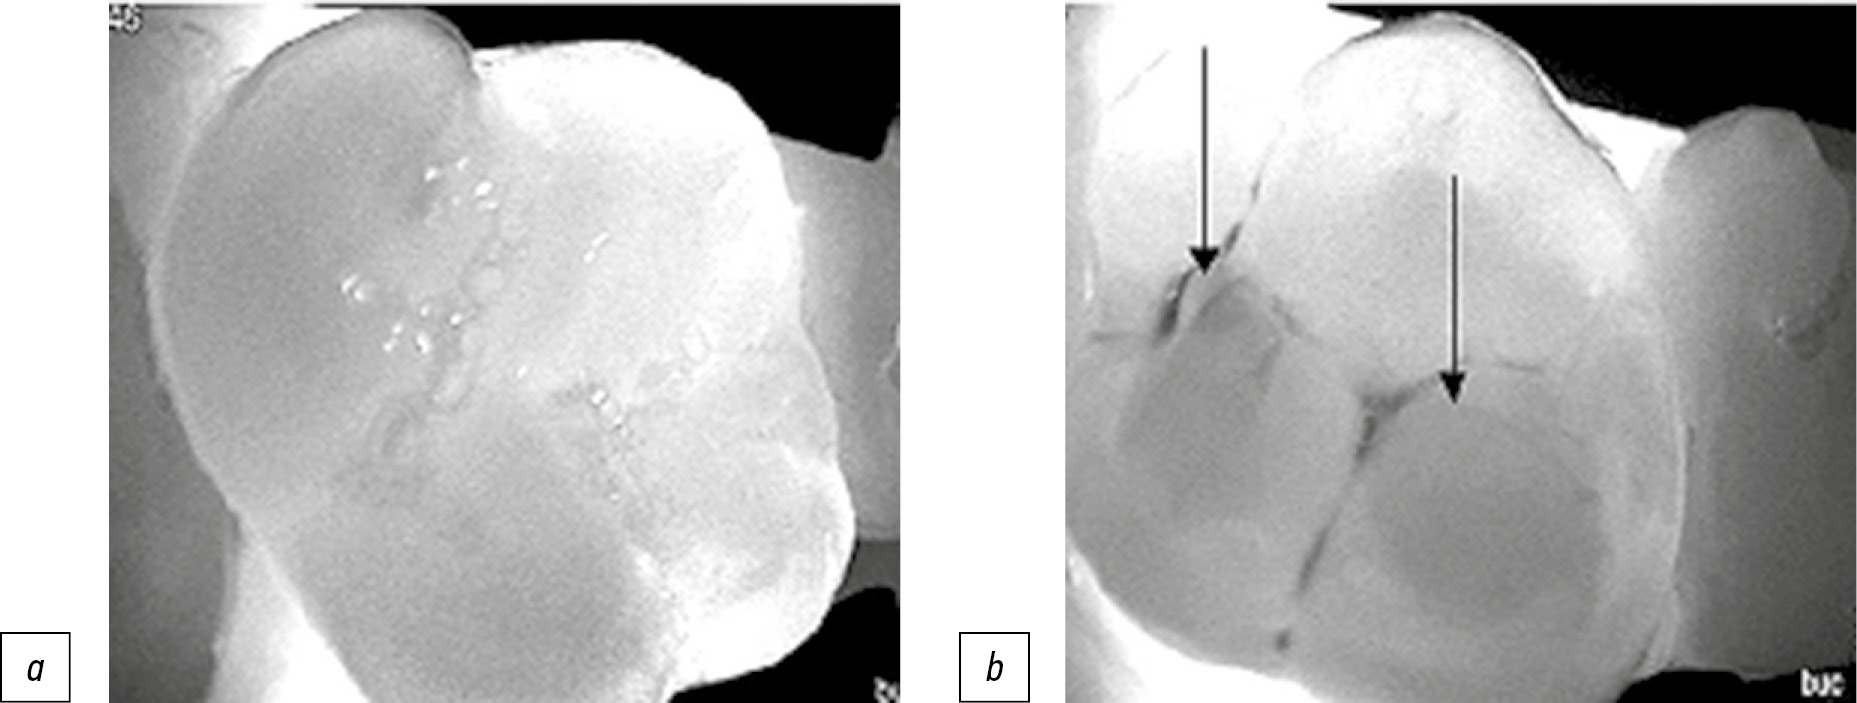

б) методом визуальной фиброоптической трансиллюминации с помощью прибора DIAGNOcam (KaVo, Германия), принцип работы которого основан на изменении цветопередачи тканей зуба при направлении лазерного источника света: здоровые ткани его пропускают, а деминерализованные участки задерживают. Цифровая внутриротовая камера фиксировала изображение и передавала на экран монитора в виде затемнённых участков различного уровня интенсивности (рис. 2).

Рис. 2. Очаги кариозного поражения, определяемые трансиллюминационным методом в режиме реального времени: а — зуб 2.6 без признаков кариозного поражения; b — зуб 1.6 с определяемыми признаками кариозного поражения в виде очагов затемнения на жевательной поверхности (показано стрелками).